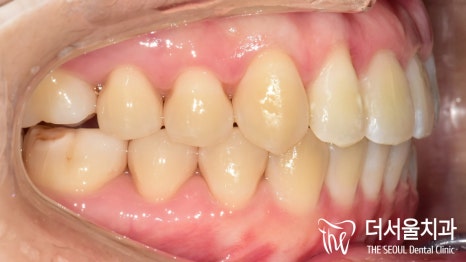

측면에서 바라보니,

앞으로 더 많이 뻐드러져 있는 것이 확인이 되죠?

이런 증세들 때문에

입술이 튀어나온 것 처럼 보여지게 되는 겁니다.

측면에서 바라봤을 때에도, 전과는 다르게

뻐드러짐이 없어진 것이 확인 됩니다.